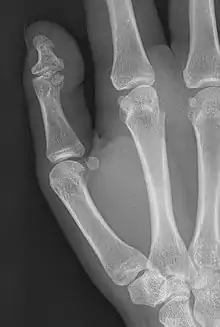

| Brachyphalangy of the thumb's distal phalanx, also known as brachydactyly type D, with otherwise normal phalanges of the 2nd-5th digits | |

This condition is caused by either fusion or early closure of the phalange's growth plate. One example is brachydactyly type D, which is caused by an early closure of the thumb's distal phalange, leading to a congenitally short thumb with a similarly short and wide thumb nail.